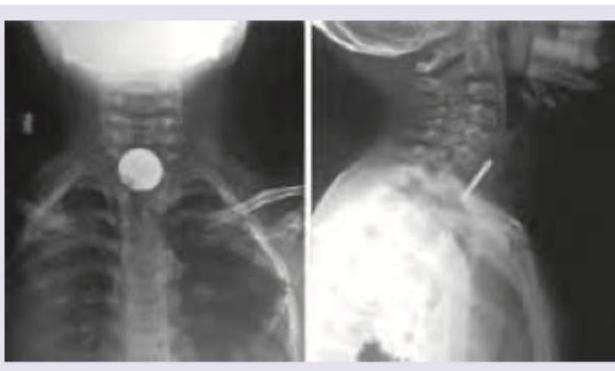

Explanation: ***Cervical esophagectomy and removal of radiopaque FB under GA is most preferred modality of treatment*** - **Cervical esophagectomy** is an extreme and highly invasive surgical procedure (removal of part or all of the esophagus) and is **never the primary treatment** for an esophageal foreign body impaction. - The standard of care for esophageal foreign body removal, particularly for radiopaque objects, is typically **endoscopic removal under general anesthesia**, not complex open surgery like esophagectomy. *Foreign body in esophagus* - The X-ray images, both anterior-posterior and lateral views, clearly show a **radiopaque, coin-shaped object** lodged in the cervical region of the neck, consistent with a foreign body. - The location and morphology of the object are consistent with impaction within the **esophagus**, as opposed to within the airway. *Most common site of impaction is cricopharynx* - The **cricopharyngeal muscle** (upper esophageal sphincter) is the narrowest part of the esophagus and is indeed the **most common site** for foreign body impaction in adults and children. - The image shows the foreign body at the level of the upper cervical spine, corresponding to the anatomical location of the cricopharynx. *Laryngeal edema* - While foreign bodies in the aerodigestive tract can potentially cause **inflammation or edema**, there is **no direct radiographic evidence of laryngeal edema** visible in these X-ray images. - Laryngeal edema would typically manifest as **soft tissue swelling** around the larynx or airway narrowing, which is not clearly depicted.